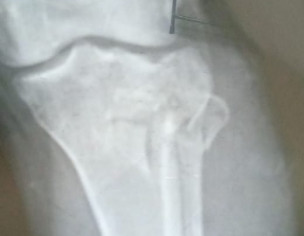

I had an accident on Thursday in which lateral condyle fracture occured.I want to ask it is need for surgery or plaster??

Attach Photo here: